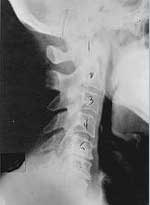

This is a side x-ray view of the neck. As with all the pictures you will see on this page, the patient is looking to the right of the screen, so you are viewing the right side of their neck. We will call this picture a "near normal" spine. Compare this spine with the ones you will see below on this page. Notice the normal forward curve of the neck. This curve helps absorb shock. Notice how each of the disc spaces between C2 (second bone in neck) and C7 are thick and even, this again is normal. Also notice how the front portions (right on the x-ray) of each of the vertebrae (called the 'body' of the vertebrae) are fairly square with clear and well defined borders. This type of arrangement is normal in the neck. Normal vertebrae in other parts of the spine also have similar characteristics to what we see here. When subluxations occur and are left uncorrected, ongoing relentless changes occur that result in damage to the structure and function of the spine along with nerve damage and the resulting problems caused from improper nerve supply.